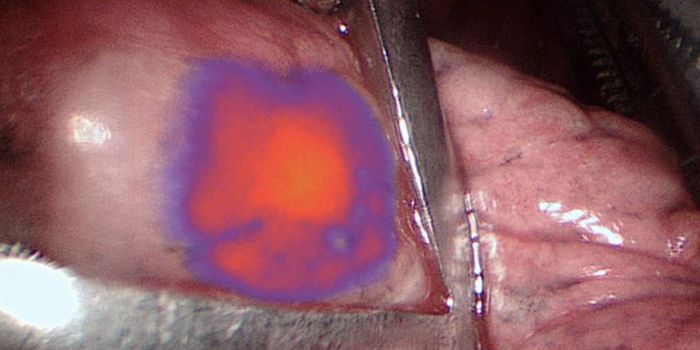

APR 03, 2018Clinical & Molecular DXScientists are improving the way PET scans work to detect diseases as early as possible with a new imaging agent. Focusi ...